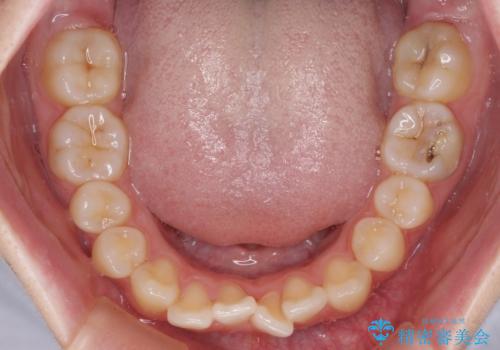

- 前歯の叢生と上顎左右の八重歯を気にして来院された患者様です。

奥歯の咬み合わせを見ると、左側は上顎が下顎に対して相対的に前方にあり、上下の前歯が接触していない状態でした。

咬み合わせを改善するためには、左側上顎臼歯を後方に移動させた咬み合わせにする必要があります。

インビザライン単体で改善することも可能性もありますが、インビザライン単体で達成する可能性が低いと考えられたため、カリエール・ディスタライザーという補助装置を併用して、より確実性を上げることとしました。

奥歯の咬み合わせを改善しながら、並行してインビザラインで歯列を整えることとしました。